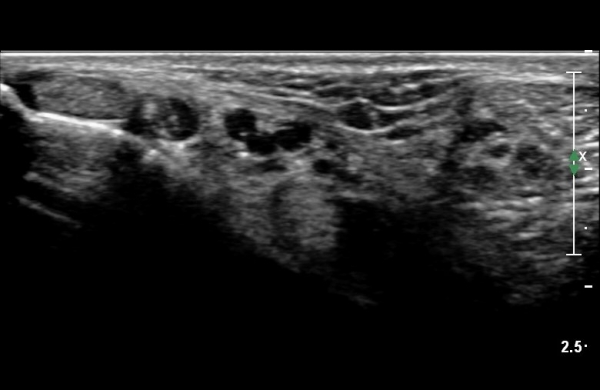

ŽÃËÀÚ¸¦ Á¶±Ý ¸»´ÜÀ¸·Î À̵¿ÇÏ´Ï Èİæ°ñ½Å°æÀÌ ³»ÃøÁ·Àú½Å°æ°ú ¿ÜÃøÁ·Àú½Å°æÀ¸·Î ºÐÁöÇÑ´Ù(»çÁø 2).